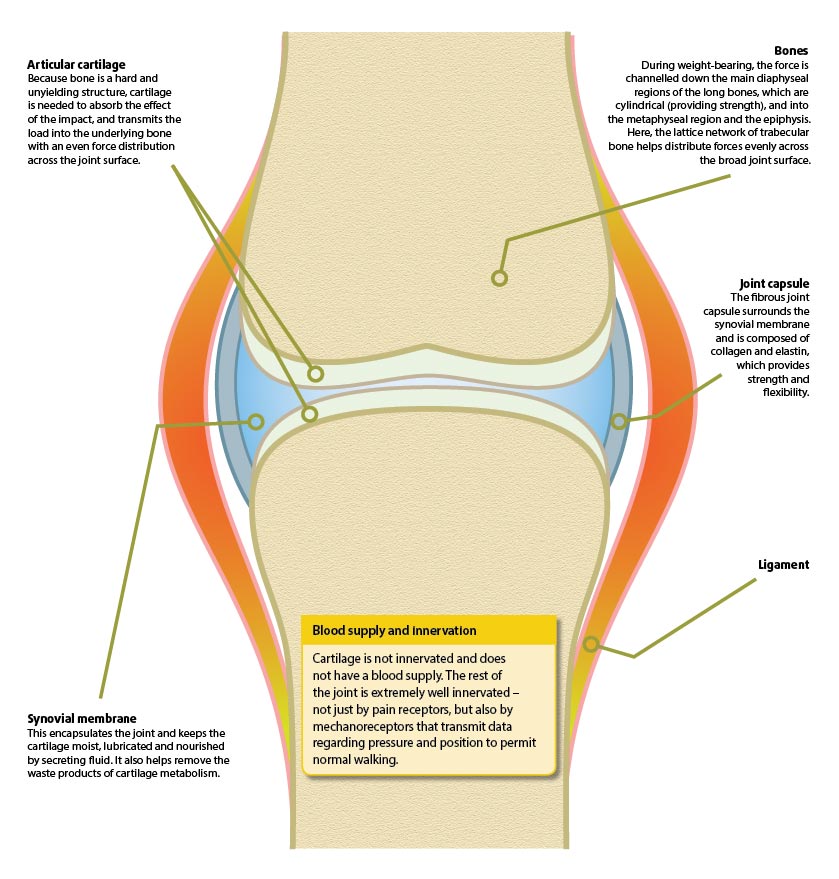

OA (also known as degenerative joint disease) can be defined as the decreased function of synovial joints due to the progressive destruction of articular cartilage, accompanied by deposition and remodelling of periarticular bone, with fibrosis of surrounding soft tissues. Superimposition of inflammation is the result of the disorder and perpetuates the destructive changes.

Joints are formed by the junction of two articulating bones; the end of each bone is covered by a specialised type of smooth and hard-wearing articular cartilage, and allows the bones to articulate with minimal friction. Its dense, compressive structure also gives it excellent shock-absorbing characteristics.

Because cartilage has a limited capacity for repair, once it is damaged, any repair will take place very slowly. Due to the lack of innervation to the cartilage, the pet will be unaware and will further exacerbate the damage by continued weight-bearing.